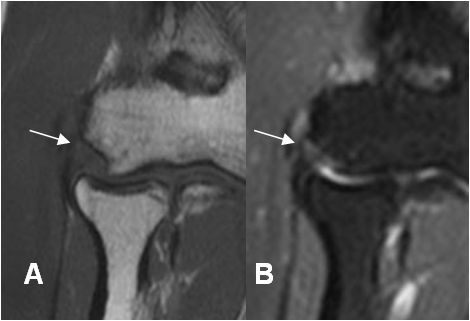

Fig 44. Esguince del LCL.

A: RM coronal en T1 y B: RM coronal en STIR. Cambios Inflamatorios rodeando el LCL, el cual permanece intacto. (Flechas).